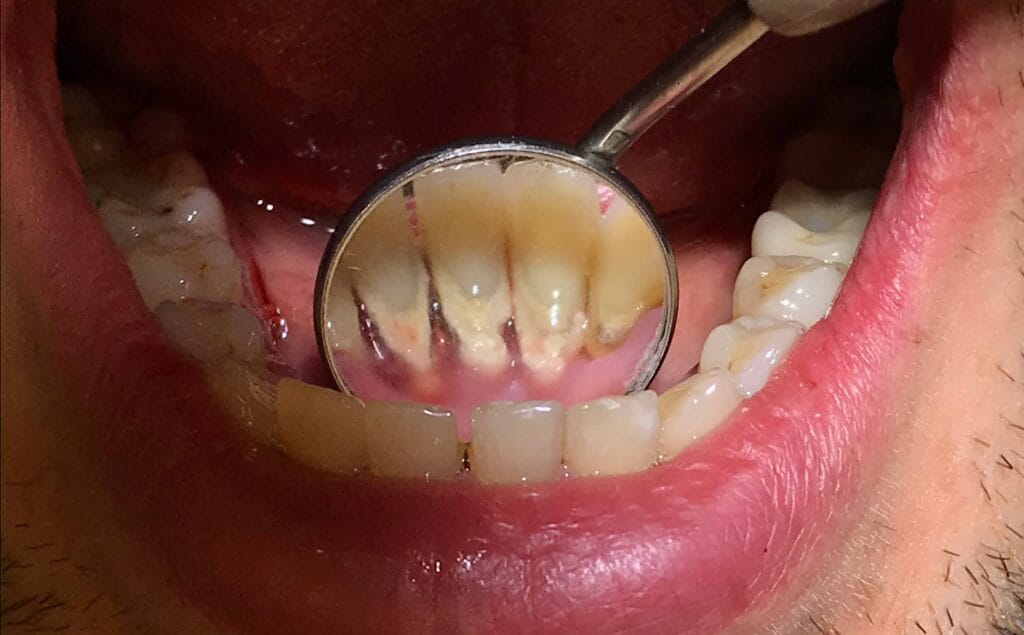

Hammaskiveä kertyy tyypillisesti erityisesti niihin kohtiin, joihin sylkeä erittyy runsaasti ja joita on vaikeampi puhdistaa itse. Tällaisia alueita ovat esimerkiksi alahampaiden sisäpinnat etuhampaiden takana sekä ylähampaiden poskihampaiden ulkopinnat. Hammaskivi voi sijaita sekä ikenen yläpuolella että ikenen alapuolella, ja sen määrä vaihtelee yksilöllisesti esimerkiksi syljen koostumuksen, hampaiden asennon ja suunhoitotottumusten mukaan.

Hammaskiveä kertyy tyypillisesti kohtiin, joihin sylkeä erittyy runsaasti. Näitä ovat erityisesti alaleuan etuhampaiden sisäpinnat ja yläleuan poskihampaiden poskipinnat. Myös ienrajan alapuolelle voi muodostua hammaskiveä, jota ei näe paljaalla silmällä.

Ienrajan alle kertynyt hammaskivi on erityisen merkityksellistä ienten terveyden kannalta. Se voi ylläpitää tulehdusta ja vaikeuttaa ienten paranemista, vaikka hampaita harjaisi säännöllisesti.